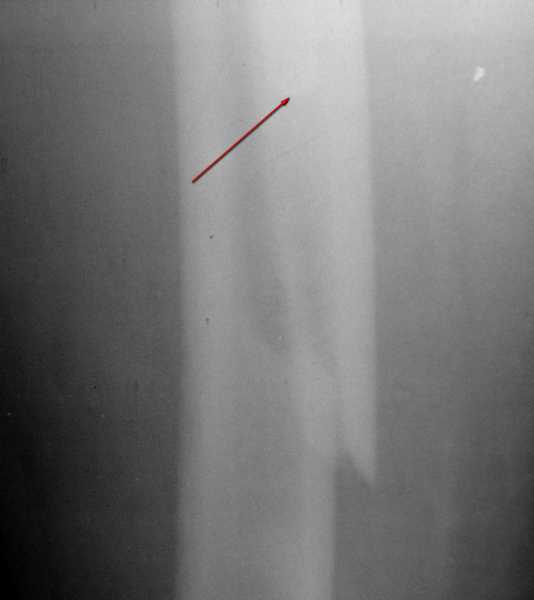

1. На снимке №3 не видны ни проксимальный отдел бедра с зоной (линией) перелома

Там видно расхождение фрагментов, диастаз чуть медиальнее б. вертела.

Снимок №4 демонстрирует дистальную линию перелома, но не показывает уровень конца ножки эндопротеза.

Кончик ножки виден на самом верху этого снимка.

Вот фрагменты этих снимков с более различимыми областями интереса.

Видимо, тут надо добиваться точной репозиции этой спирали вдоль протеза, чтобы воссоздать ложе для ножки.